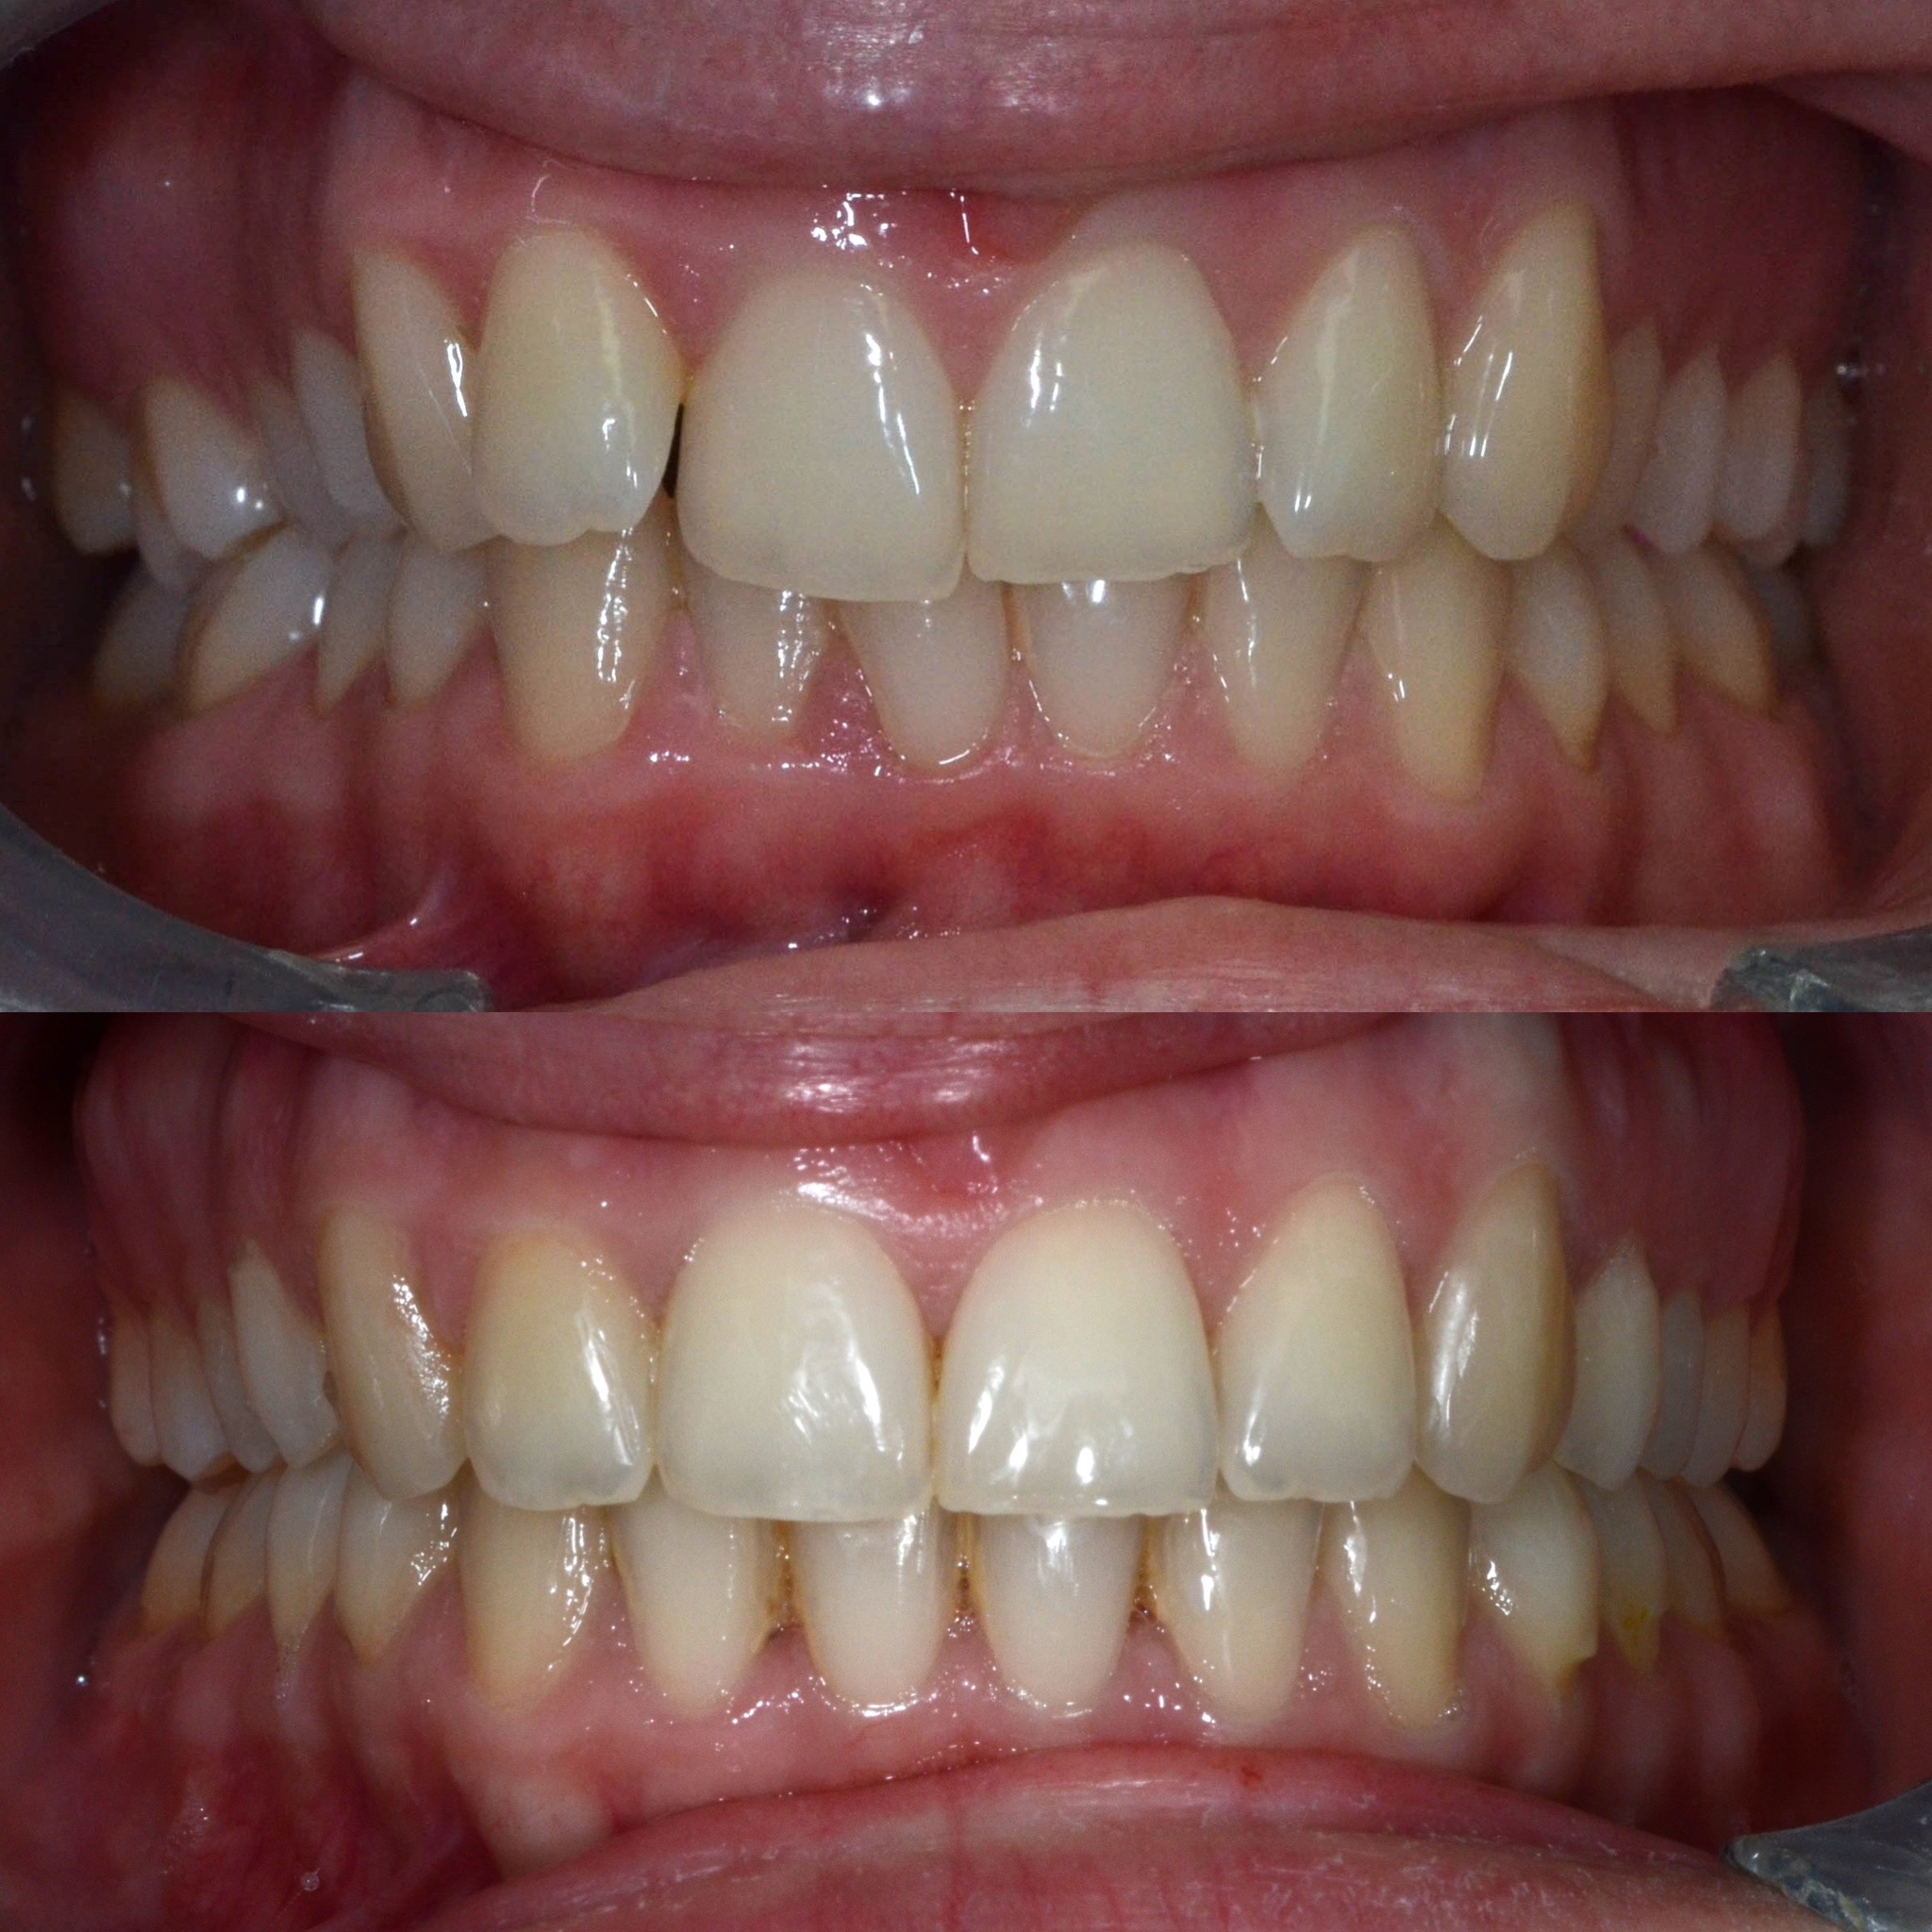

U galeriji slika su prikazani klinički slučajevi ovakvih odraslih pacijenta bilo da se radi samo o ortodontskoj terapiji ili predprotetskoj ortodonciji.

Na sljedećoj slici se mogu vidjeti početak i kraj ortodontske i protetske terapije. Protetske radove radio je dr. Goran Radica.

Na sljedećoj slici mogu se vidjeti početak i kraj ortodontske terapije. Pacijentica je upućena od svog stomatologa nakon što nije bila zadovoljna izgledom osmjeha i odnosom zuba i gingive u privremenom protetskom radu. Napravljena je ortodontska terapija samo u gornjoj čeljusti a nakon toga novi privremeni protetski rad.